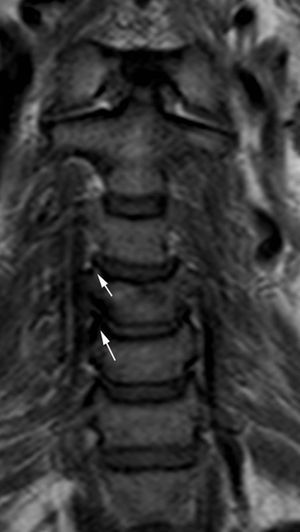

Depósitos de pirofosfato cálcicoLos depósitos de pirofosfato cálcico (CPPD) pueden verse en varias estructuras, como los discos intervertebrales, ligamentos, bursas, cartílago articular, sinovial y cápsulas articulares. Es frecuente su localización en la articulación atlanto-axoidea, donde se puede depositar en el ligamento transverso y sinovial, y asociar una artropatía erosiva. Se asocia con aumento de partes blandas retrodontoideas (fig. 15, fig. 15b online)41.